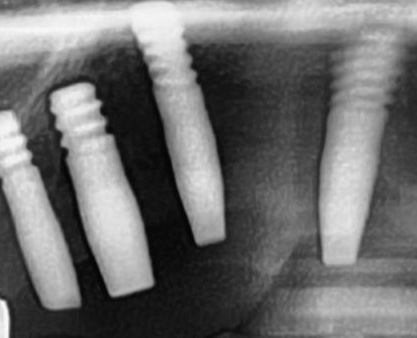

今回の患者様はインプラント植立を希望され、右上1番目・2番目の2本の植立が決まりました。

開けた穴に、専用道具を使ってネジを締めるように長さ2センチ程のインプラントを骨に埋め込んでいきます。

続けて他の歯も同じように植立していきます。

インプラントオペでは、複数本を植立する場合でも、当時進行はせず、1本ずつ同じ工程を繰り返して植立します。

しっかりとインプラント埋め込まれた後は、動揺がないか、噛んだ時に当たらないかなどを確認して、最後にパノラマ写真を撮影して今回のオペは終了となりました。